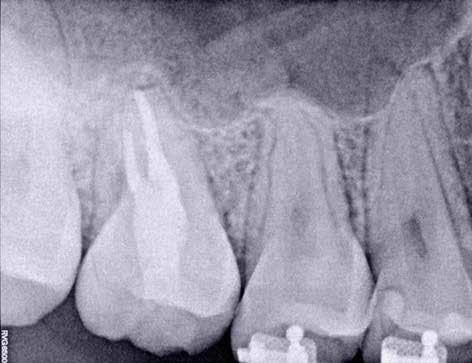

10. ábra: A periapikális felvételen egyértelműen megmutatkozik a 46-os és 47-es fogak között kialakult csontos defektus, valamint a gyökereket fedő parodontális rostok károsodása. – 11. ábra: A disztális gyökér amputációját követően a csonthiány kiterjedése látszólag tovább növekedett. – 12. ábra: A 22 évvel később készített kontrollfelvételen jól megfigyelhető a csontos defektus telődése, valamint új kortikális csontállomány kialakulása.

Gyökéramputációt főként a furkáció érintett nagyőrlő fogak ellátása során szoktunk alkalmazni. Derks és mtsai. vizsgálatában a gyökéramputált nagyőrlő fogak közel 80%-a 20 évvel a beavatkozás elvégzését követően is megtartott volt. 1998 októberében egy 39 éves férfi páciens a jobb alsó kvadránsban jelentkező ínyérzékenység miatt kereste fel rendelőnket. A klinikai vizsgálat során jobb alsó első és második nagyőrlő fog között (46–47) nagy kiterjedésű csontveszteséget észleltünk. Ettől eltekintve a teljes fogazat parodontális státusza megfelelőnek bizonyult. A jobb alsó kvadránsban végzett szenzibilitás vizsgálat során arra az eredménye jutottunk, hogy a 46-os fog vélelmezhetően elhalt (10. ábra).

A páciens beleegyezését követően a 46-os fog disztális gyökere, a disztális gyökér felett lévő koronális rész megőrzése mellett rezekcióra került (11. ábra). A rezekciót követően a referáló orvos a 46. és 47. fogak koronáját Ribbond szalag és kompozit segítségével egymáshoz rögzítette. A sebészi beavatkozást követően 22 évvel készült kontrollfelvételen a lézió csontos telődése, kortikális csontállomány kialakulása, valamint a furkáció körüli csontos regeneráció volt megfigyelhető (12. ábra) A károsodott fogak megtartására szolgáló lehetőségek fejlődésének, valamint az implantátumok behelyezésével kapcsolatos rizikófaktorok jobb megértésének köszönhetően ma már más szemmel vizsgáljuk a fogak eltávolításának szükségességét. A kérdéses prognózissal vagy a kis protetikai értékkel rendelkező fogak eltávolítása előtt mindig érdemes felmérni az ezzel elérhető lehetséges előnyök nagyságát. A kemény- és lágyszöveti pótlás lehetőségeinek fejlődésével, a PRF elérhetőségével, a minimálinvazív sebészeti módszerek és az operációs mikroszkópok elterjedésével, valamint a varróanyagok és varrat technikák egyre kifinomultabbá válásával ma már alaposan el kell gondolkodnunk az előtt, hogy egy fogat egy implantátum behelyezése érdekében eltávolítsunk. Mára sokkal kedvezőbb prognózist és sokkal nagyobb sikerességet tudunk elérni a korábban menthetetlennek gondolt fogak kezelése során.